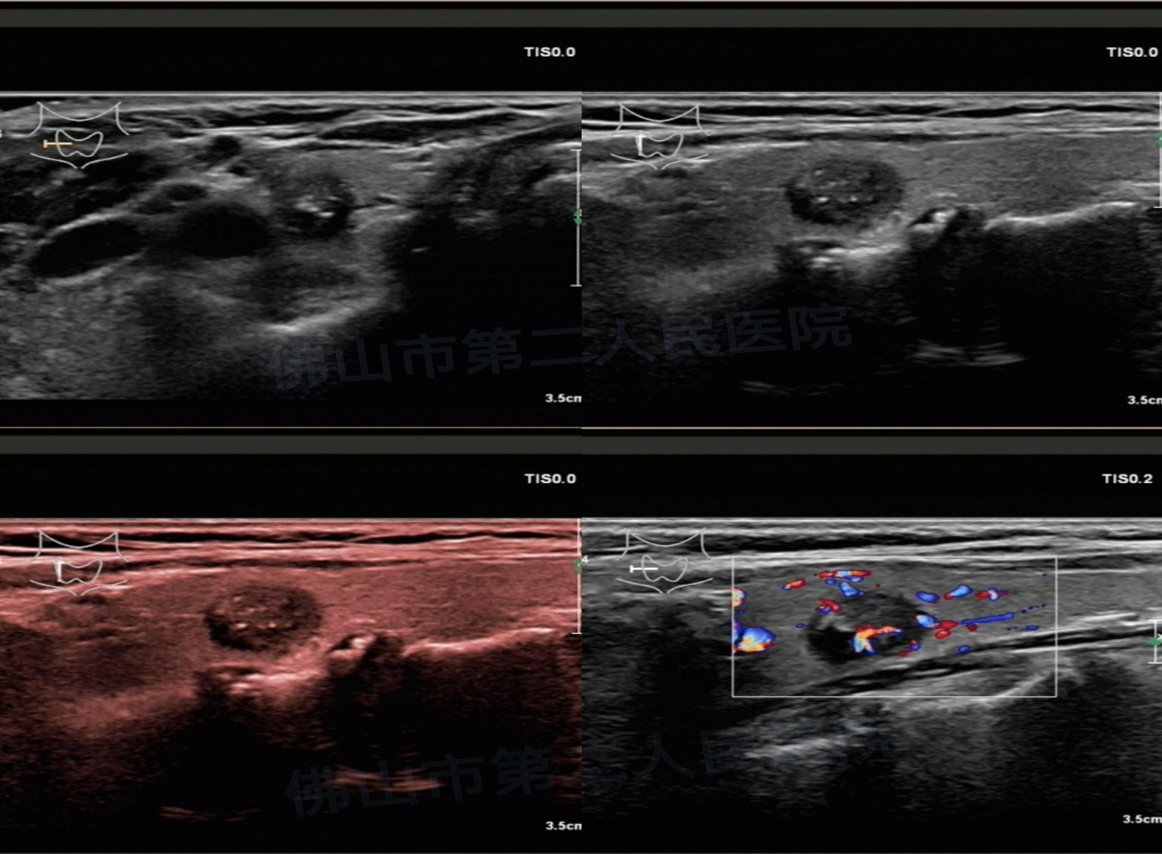

(病例1:恶性结节,实性,低回声,纵横比>1,点状及粗大钙化)